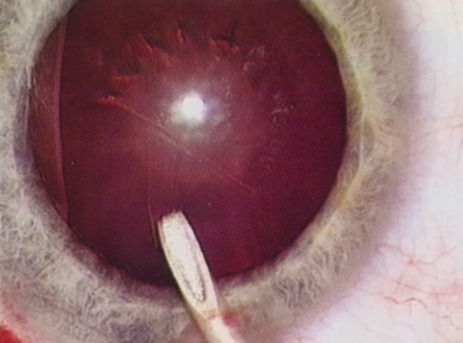

Retrobulbar blocks were among the earliest of orbital block techniques and have stood the test of time. Although there are many approaches to block administration, each technique intends delivery of the anesthetic medication into the intraconal space. These blocks are highly effective (about 95%) in achieving adequate ocular akinesia and anesthesia. Potential complications include retrobulbar hemorrhage,67 globe penetration,68,69 optic nerve sheath hemorrhage, extraocular muscle toxicity with persistent diplopia, and, rarely, brainstem anesthesia. Visualization of the globe is improved when using a transconjunctival approach (Fig. 6) or when the skin is indented with a cotton-tipped applicator (Fig. 7), making globe perforation less likely.

Fig. 7. The skin is indented with a sterile cotton-tipped applicator until it is past the equator of the globe, thereby reducing the risk of globe perforation when the needle is inserted.